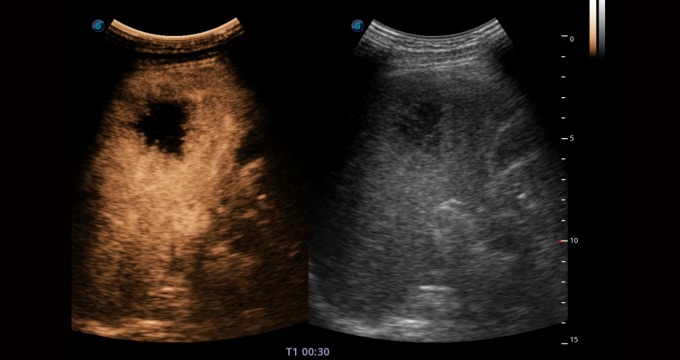

造影成像功能和定量分析工具包使医生能够准确的评估血流灌注情况。独特的动态声压控技术有效控制造影剂的声压,保证造影剂持续时间,方便医生观察病变灌注的延迟相位。